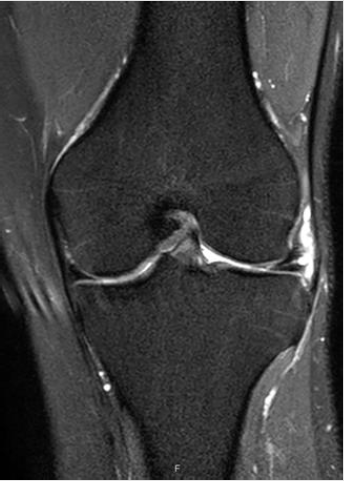

Figure 5: LMT (thick arrow) and parameniscal cyst (thin arrow) as seen in MRI (same patient as in Figure 4).

Out of all patients who underwent US, 24 (7.0%) have done also MRI, 6 (25%) had LMT and 14 (58.3%) had MMT. In 28 (7.8%) there was no pathology detected in US or MRI?. The sensitivity for MMT was 78.5% and specificity of 70.0%, PPV 78.5% and NPV of 70.0%. For LMT sensitivity was 50.0% and specificity of 94.4%, PPV 75.0% and NPV of 85.0%. The calculations were made based on comparison with the MRI results, which considered the gold standard non-invasive test for detection of meniscal tears (Tables 1 & 2). Arthroscopy was performed in 7 (2.5%) patients: in 3 (42.9%) was LMT and in 5 (71.4%) MMT. Because of these low numbers of patients, we couldn’t calculate the sensitivity and specificity in comparison to arthroscopy. In those who passed MRI, we found high relations between: MMT seen in MRI and in US (P=0.016) and degenerative changes in US (P=0.032). LMT seen in MRI and in US (P=0.010) and lateral subluxation in US (P=0.009). Also, there was a trend toward relation between para-meniscal cyst and LMT (P=0.08) (Figures 2-12).